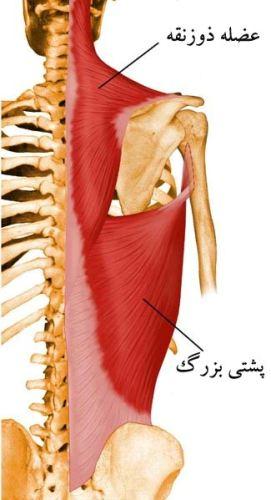

عضله ذوزنقه

این عضله پهن و حجیم سطح زیادی از پشت را می پوشاند. با توجه به وسعت و حجمی که دارد اعمال زیادی را نیز عهده دار است. به همین علت قسمت های مختلفی در عضله قابل تشخیص هستند.

الف: تارهای قسمت فوقانی عضله از سطح خارجی صدف استخوان پس سری شروع شده و به یک دوم خارجی در سطح خلفی ترقوه متصل می شود.

ب: تارهای بعدی از لیگامنت نوکه (در پشت گردن) شروع شده و به زائده اخرمی دو استخوان کتف ارتباط پیدا می کنند.

ج: دسته های بعدی تارها از خارهای هفتمین مهره گردنی و مهره های فوقانی پشتی شروع شده و به خارهای استخوان های کتف متصل می شوند.

د: تارهای تحتانی این عضله از روی خارهای بقیه مهره های پشتی شروع شده و به انتهای داخلی خار کتف (ریشه خار) در هر طرف متصل می شوند.

عضله پشتی بزرگ

این عضله نیز از عضلات بزرگ پشت بوده و سطح وسیعی را می پوشاند. قسمت فوقانی این عضله توسط قسمت تحتانی عضله ذوزنقه پوشانده می شود. عضله پشتی بزرگ از روی خارهای شش مهره تحتانی پشتی و تمام مهره های کمری و سطح خلفی خاجی و قسمت خلفی تاج خاصره در هر طرف، زاویه تحتانی کتف و سه یا چهار دنده تحتانی، شروع می شود. تارهای عضله به طرف فوقانی و خارج کشیده شده و به وسیله یک تاندون بلند به قسمت قدامی استخوان بازو ( انتهای تحتانی ناودان دوسری) چسبندگی پیدا می کنند.